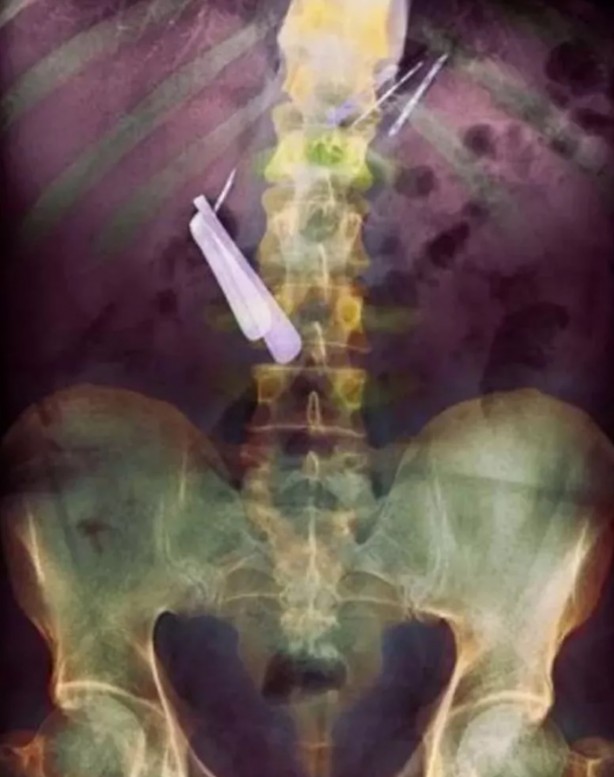

Bu resimdeki hastanın bağırsağında bir diş fırçası, iki çatal ve bir tükenmez kalem var...